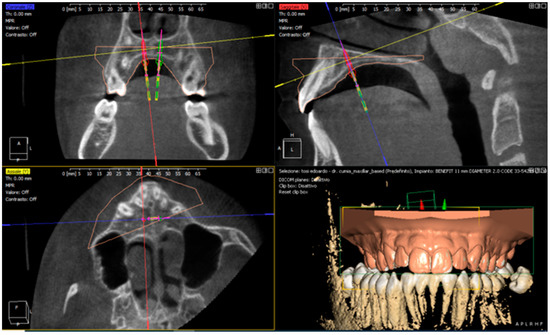

- Graf, S.; Vasudavan, S.; Wilmes, B. CAD-CAM design and 3-dimensional printing of mini-implant retained orthodontic appliances. Am. J. Orthod. Dentofac. Orthop. 2018, 154, 877–882. [Google Scholar] [CrossRef] [PubMed] [Green Version]

- Neumeister, A.; Schultz, L.; Glodecki, C. Investigations on the accuracy of 3D-printed drill guides for dental implantology. Int. J. Comput. Dent. 2017, 20, 35–51. [Google Scholar]